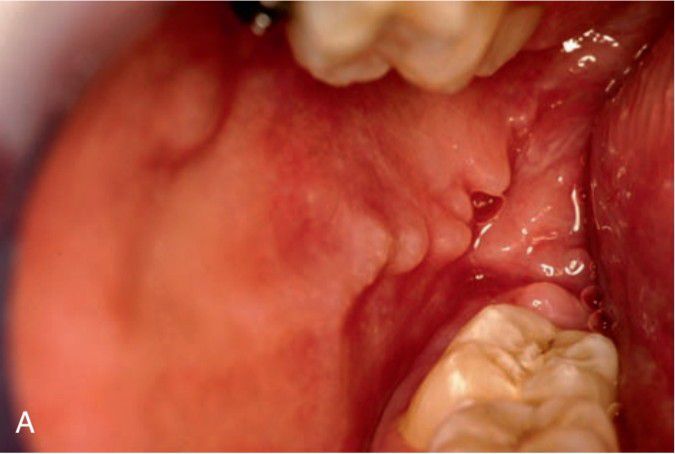

Nodules and ulcers of Crohn’s disease.

Oral manifestations of crohn's disease include mucosal fissures and small, multiple, hyperplastic nodules on the buccal mucosa,producing a cobblestone appearance.